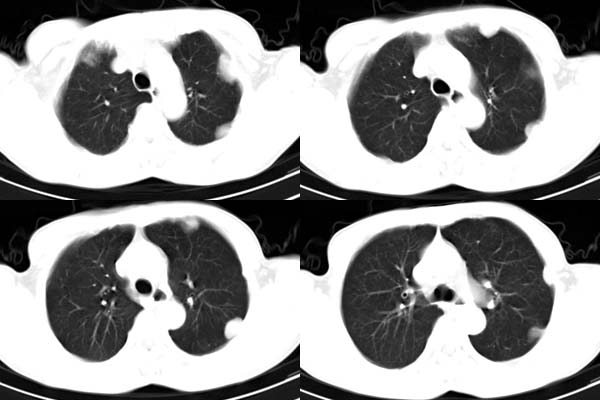

患者,男,65岁,咳嗽,胸痛

ct所见;左下肺可见片状阴影,密度不均,边缘尚清晰,胸膜方向见有条索相连,纵隔窗未见具体结节。左侧胸膜下见多个软组织结节且以宽基底与胸膜相连,右侧胸锁关节层面亦见软组织结节广基与胸膜相连。纵隔未见肿大淋巴结,气管,支气管开口正常。

左肺下叶基底段见结节样稍高密度影,内密度不均匀,边缘不清,可见索条影与邻近胸膜粘连,左侧胸膜上见多个结节影,以宽基底与胸膜粘连.纵隔不宽,内未见明确肿大的淋巴结.

考虑:周围型肺ca伴左侧胸膜转移可能性大 ,不完全除外左肺下叶炎性假瘤,左侧胸膜间皮瘤可能,建议强化ct扫描。

ct所见:左肺上、下叶近胸膜肺外带可见多个大小不等的结节灶,边界清楚,边缘比较光整。近胸膜病灶似与胸膜以宽基底紧连。提供的病史比较简单,我考虑:1、胸膜原发肿瘤可能性大(就形态来看恶性可能性不大);那么大胆的设想一下,左下叶结节是否与它有必然的联系呢?也可以是结核或周围型肺癌。2、还可以考虑为胸膜和肺内的都是转移灶,病人65岁,是不是其他部位的恶性肿瘤转移过来的呢?因为病灶比较表浅,但一侧发病较少见。3、周围型肺癌并胸膜转移的可能性比较小,一是肺内病灶较小,单发,胸膜结节相对较多,位置较远,临近胸膜无受侵。